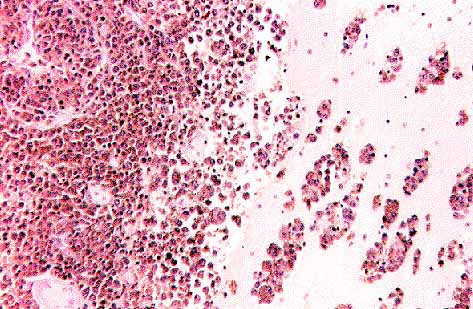

Figura 9.Tinción para antigeno leucocitario común. Infiltración exclusivamente subarcnoidea.

Figura 13. Tinción positiva para el L-26, infiltración del parenquima. x40

Figura 14. Tinción para UCHL1(CD45RO) positiva en los linfocitos pequeños pero negativa en los grandes. x20

Figura 15. Tinción para cadena ligera kappa(lambda similar)x20. Los linfocitos neoplasicos son negativos(una células plasmática positica como control interno)